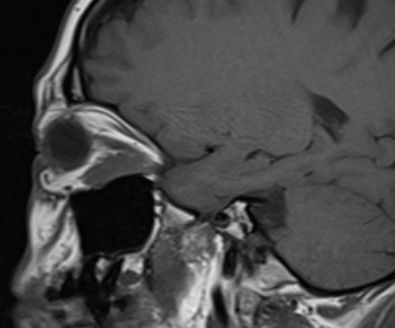

MRT eines retroorbitalen Lymphoms |